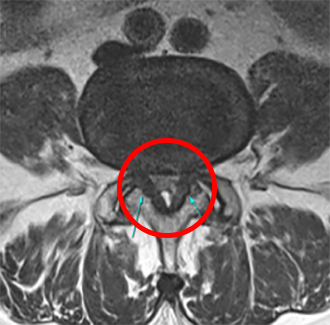

탈출된 디스크로 인해 신경근이 눌리면 허리나 다리통증을 유발할 수 있다.

파열된 디스크 조각이 까맣게 신경 속으로 들어가 있다.

파열 파편만 없어지고 정상디스크 쿠션은 하얗게 보존되어 있다.

디스크 높이가 20년동안 그대로 유지된 모습